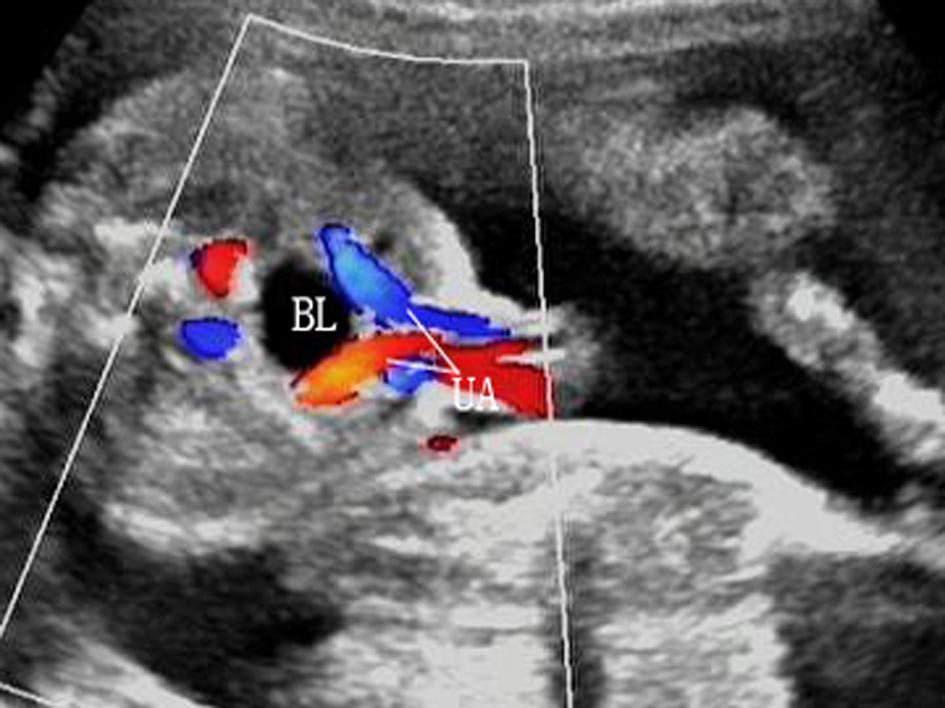

3.膀胱 显示为盆腔内圆或椭圆形无回声区(图7 BL)。正常情况下早孕晚期开始产生尿液,孕13周以后可显示为典型的无回声区,脐动脉腹腔段的显示有助于对评估的辨认。正常膀胱每20~45min充盈和排空一次,孕15周可清晰显示。膀胱容量不定,过度充盈时,要在30~45min后复查以排除尿路梗阻。

图7胎儿膀胱横切面声像图

脐带进出腹腔的部位及其周围腹壁完整性是前腹壁超声检查的重要内容[6, 21]。正常时腹壁的肌肉层回声比较低,应当关注与可能存在的胎儿腹腔积液或假性胎儿腹腔积液鉴别[52]。在脐部可以显示一根较粗的脐静脉和两根稍细的脐动脉,二维超声检查和CDFI检查均可显示脐动脉与膀胱的关系。局部腹壁与脐带三根血管关系明确、清晰,不应显示膨出或混有其他回声。